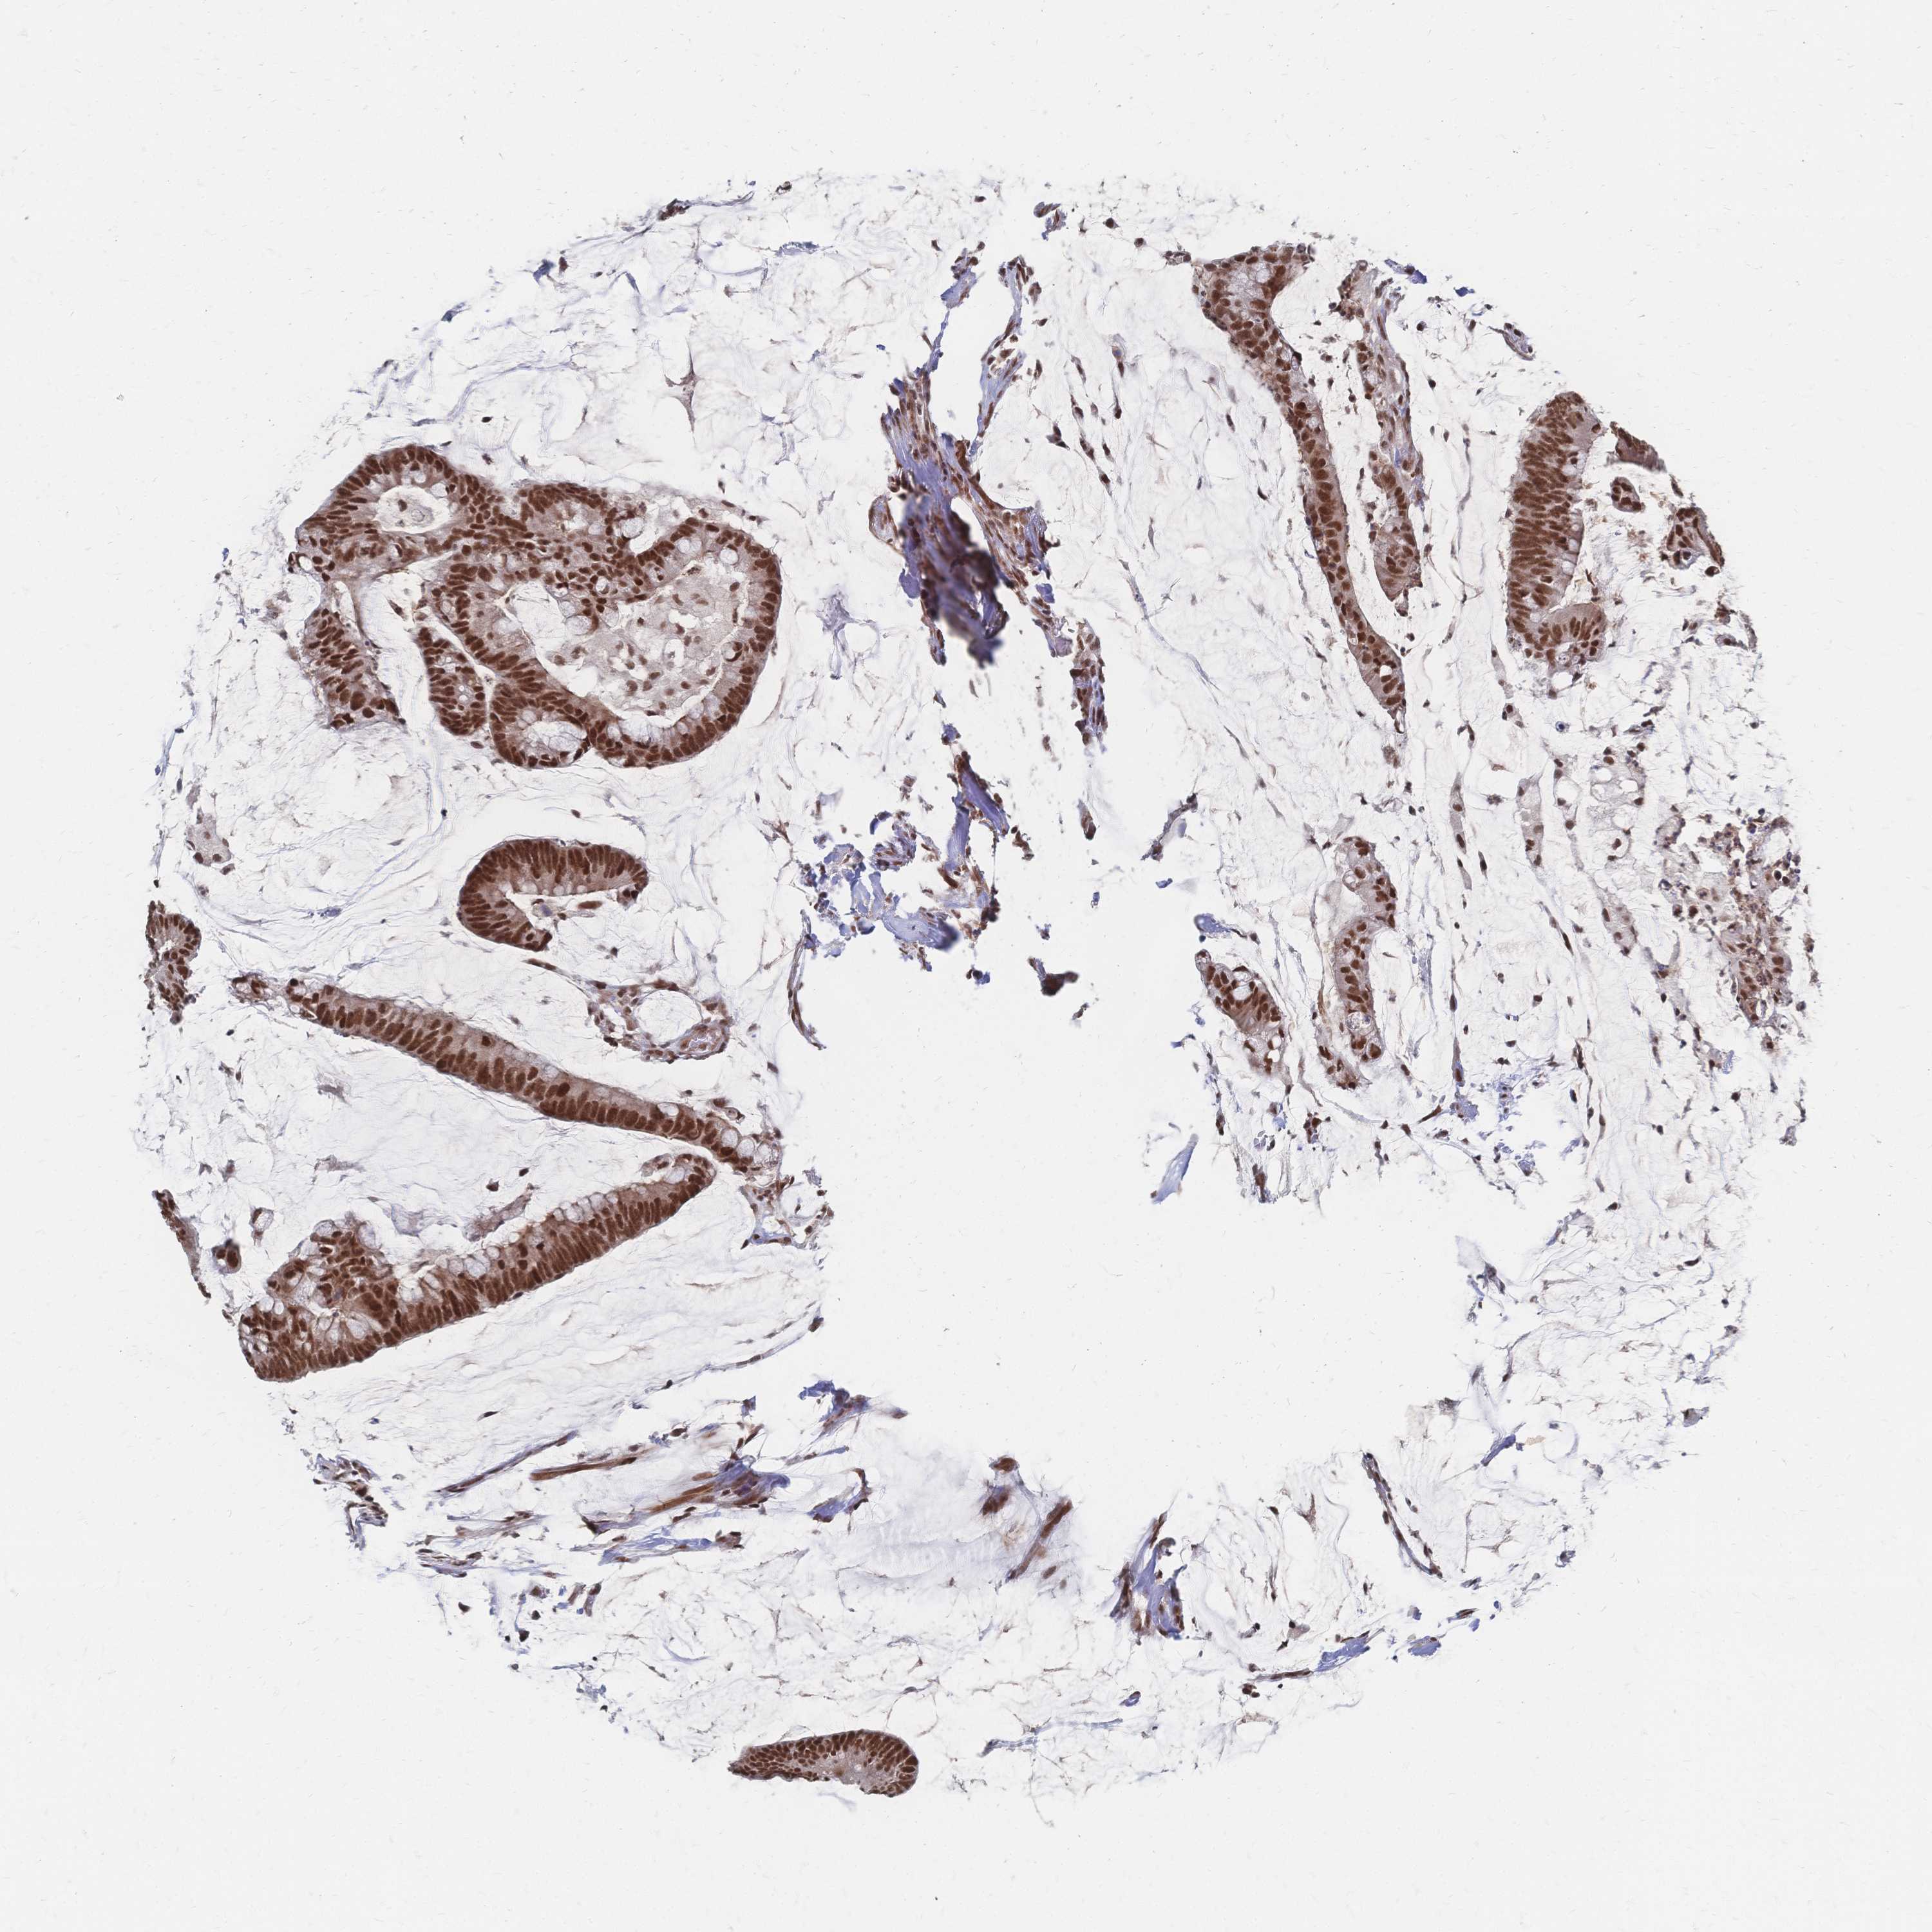

CANCER COLORECTAL CANCER Show tissue menu

Colorectal cancer

Human cancer

Colon adenocarcinoma